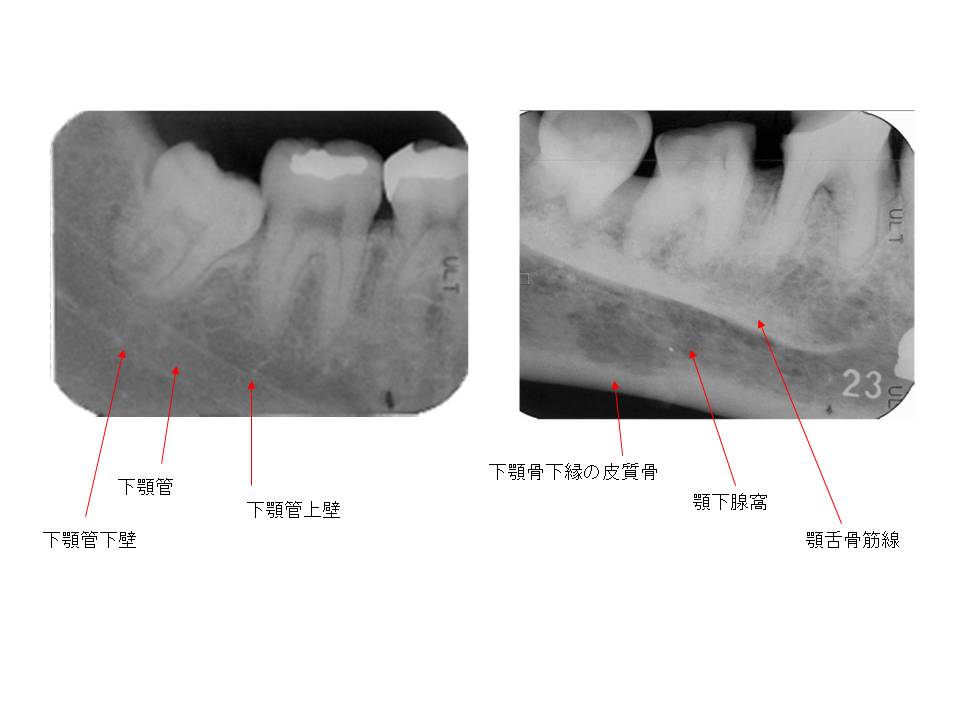

口内法(二等分法・咬合法)撮影の解剖